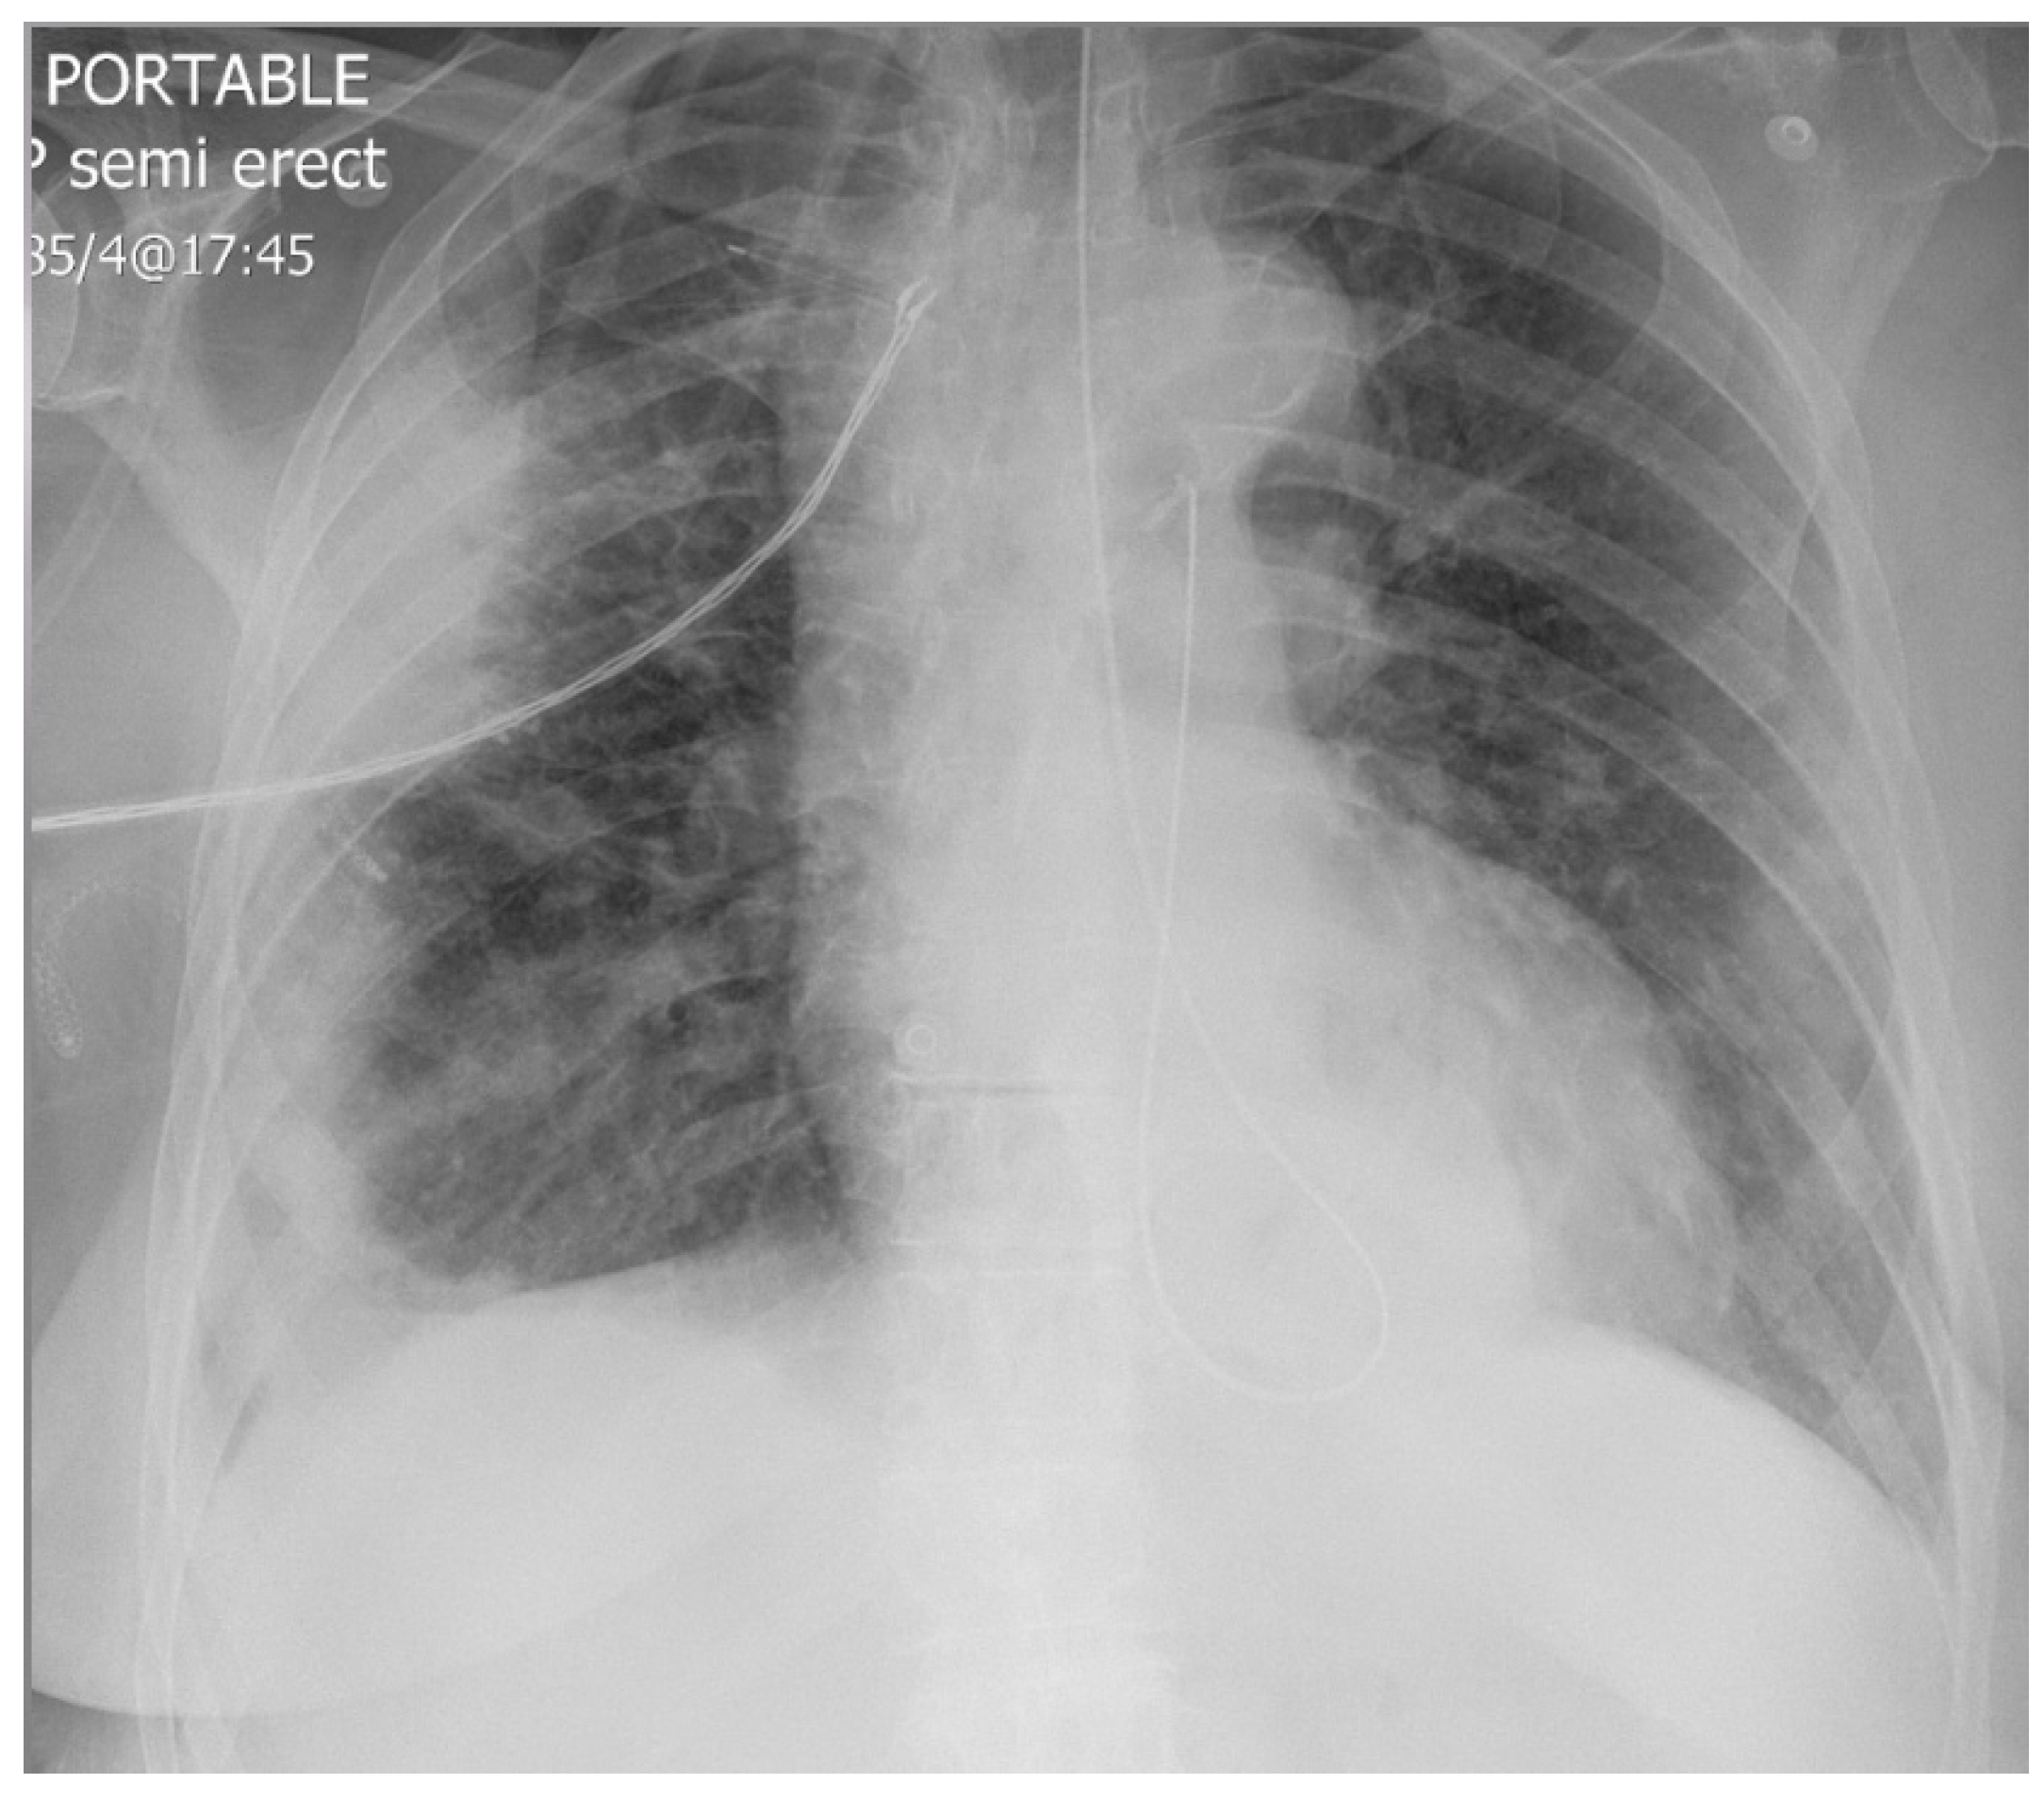

3.1. Data Set Description

Image Augmentation with Keras ImageDataGenerator Class